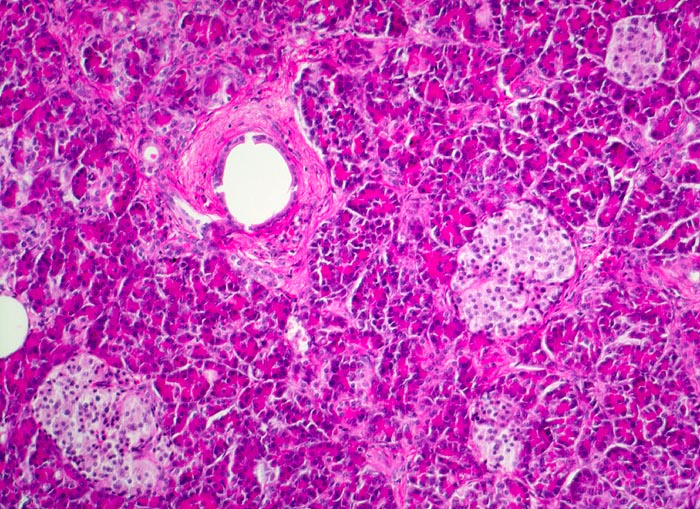

Normales endokrines Pankreas: Langerhans Inseln

Rundliche helle Zellinseln im Pankreasparenchym. Die Inselzellen sind kleiner und blasser als die Azinuszellen. Sie sind zu kleinen Gruppen (Inseln) innerhalb der exokrinen Azini angeordnet. Im Bildzentrum ein kleiner Ausführungsgang.

Die Langerhans Inseln sind am zellreichsten im Schwanzbereich und können sehr unterschiedlich gross sein. Zelltypen: 70% B-Zellen bilden Insulin und Amilin, 20% A-Zellen bilden Glukagon, 5-10% D-Zellen bilden Somatostatin, 1-2% PP-Zellen bilden pankreatisches Polypeptid. Die übrigen Zellen bilden VIP oder gemischte Sekrete (Enterochromaffine Zellen).